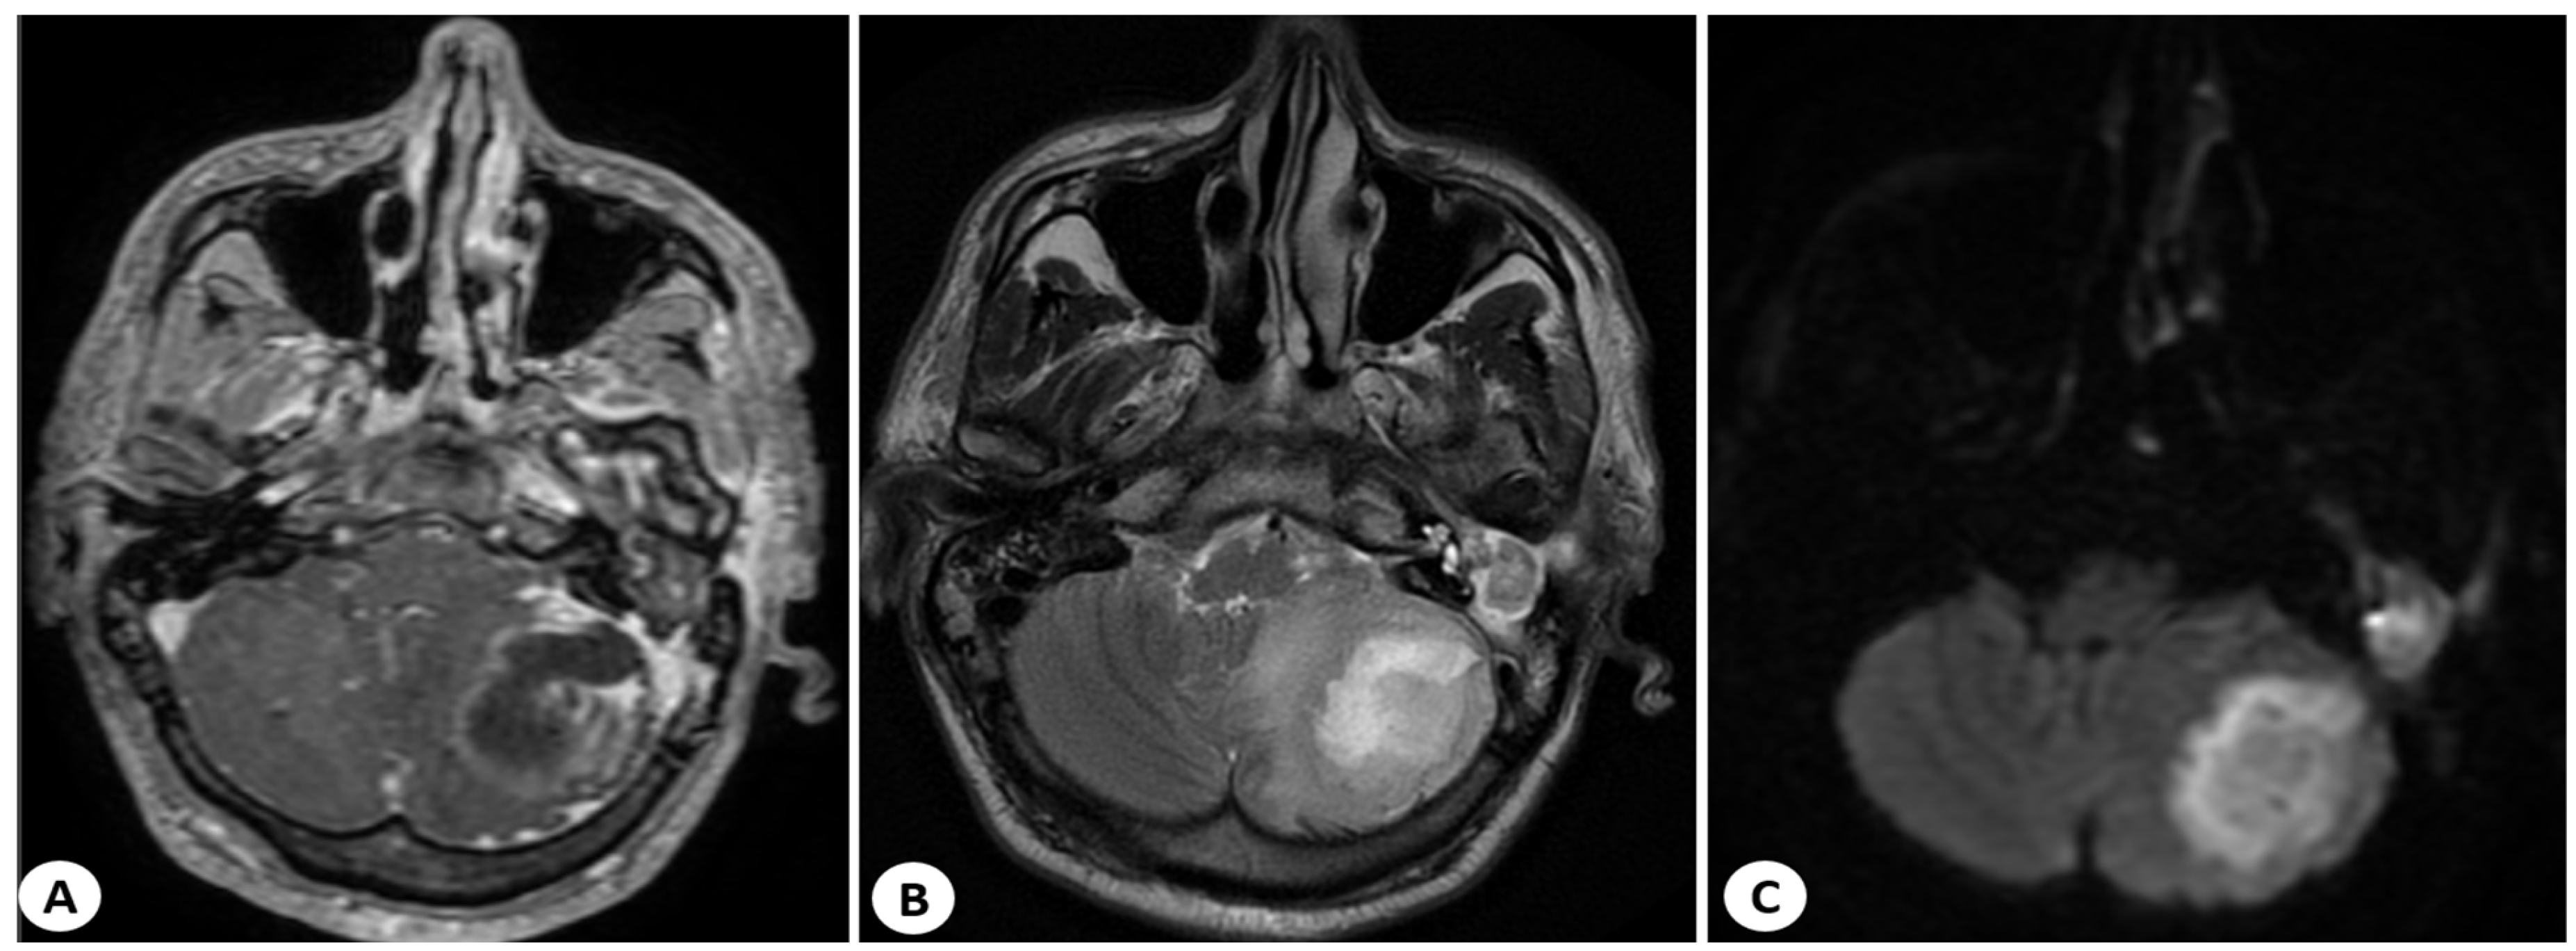

Furthermore, the contrast-enhanced CT scan revealed a left cholesteatomatous otomastoiditis (Figure 2).

Figure 2. Contrast-enhanced CT scan (axial, sagittal and coronal planes) showing a left cholesteatomatous otomastoiditis (red arrow).